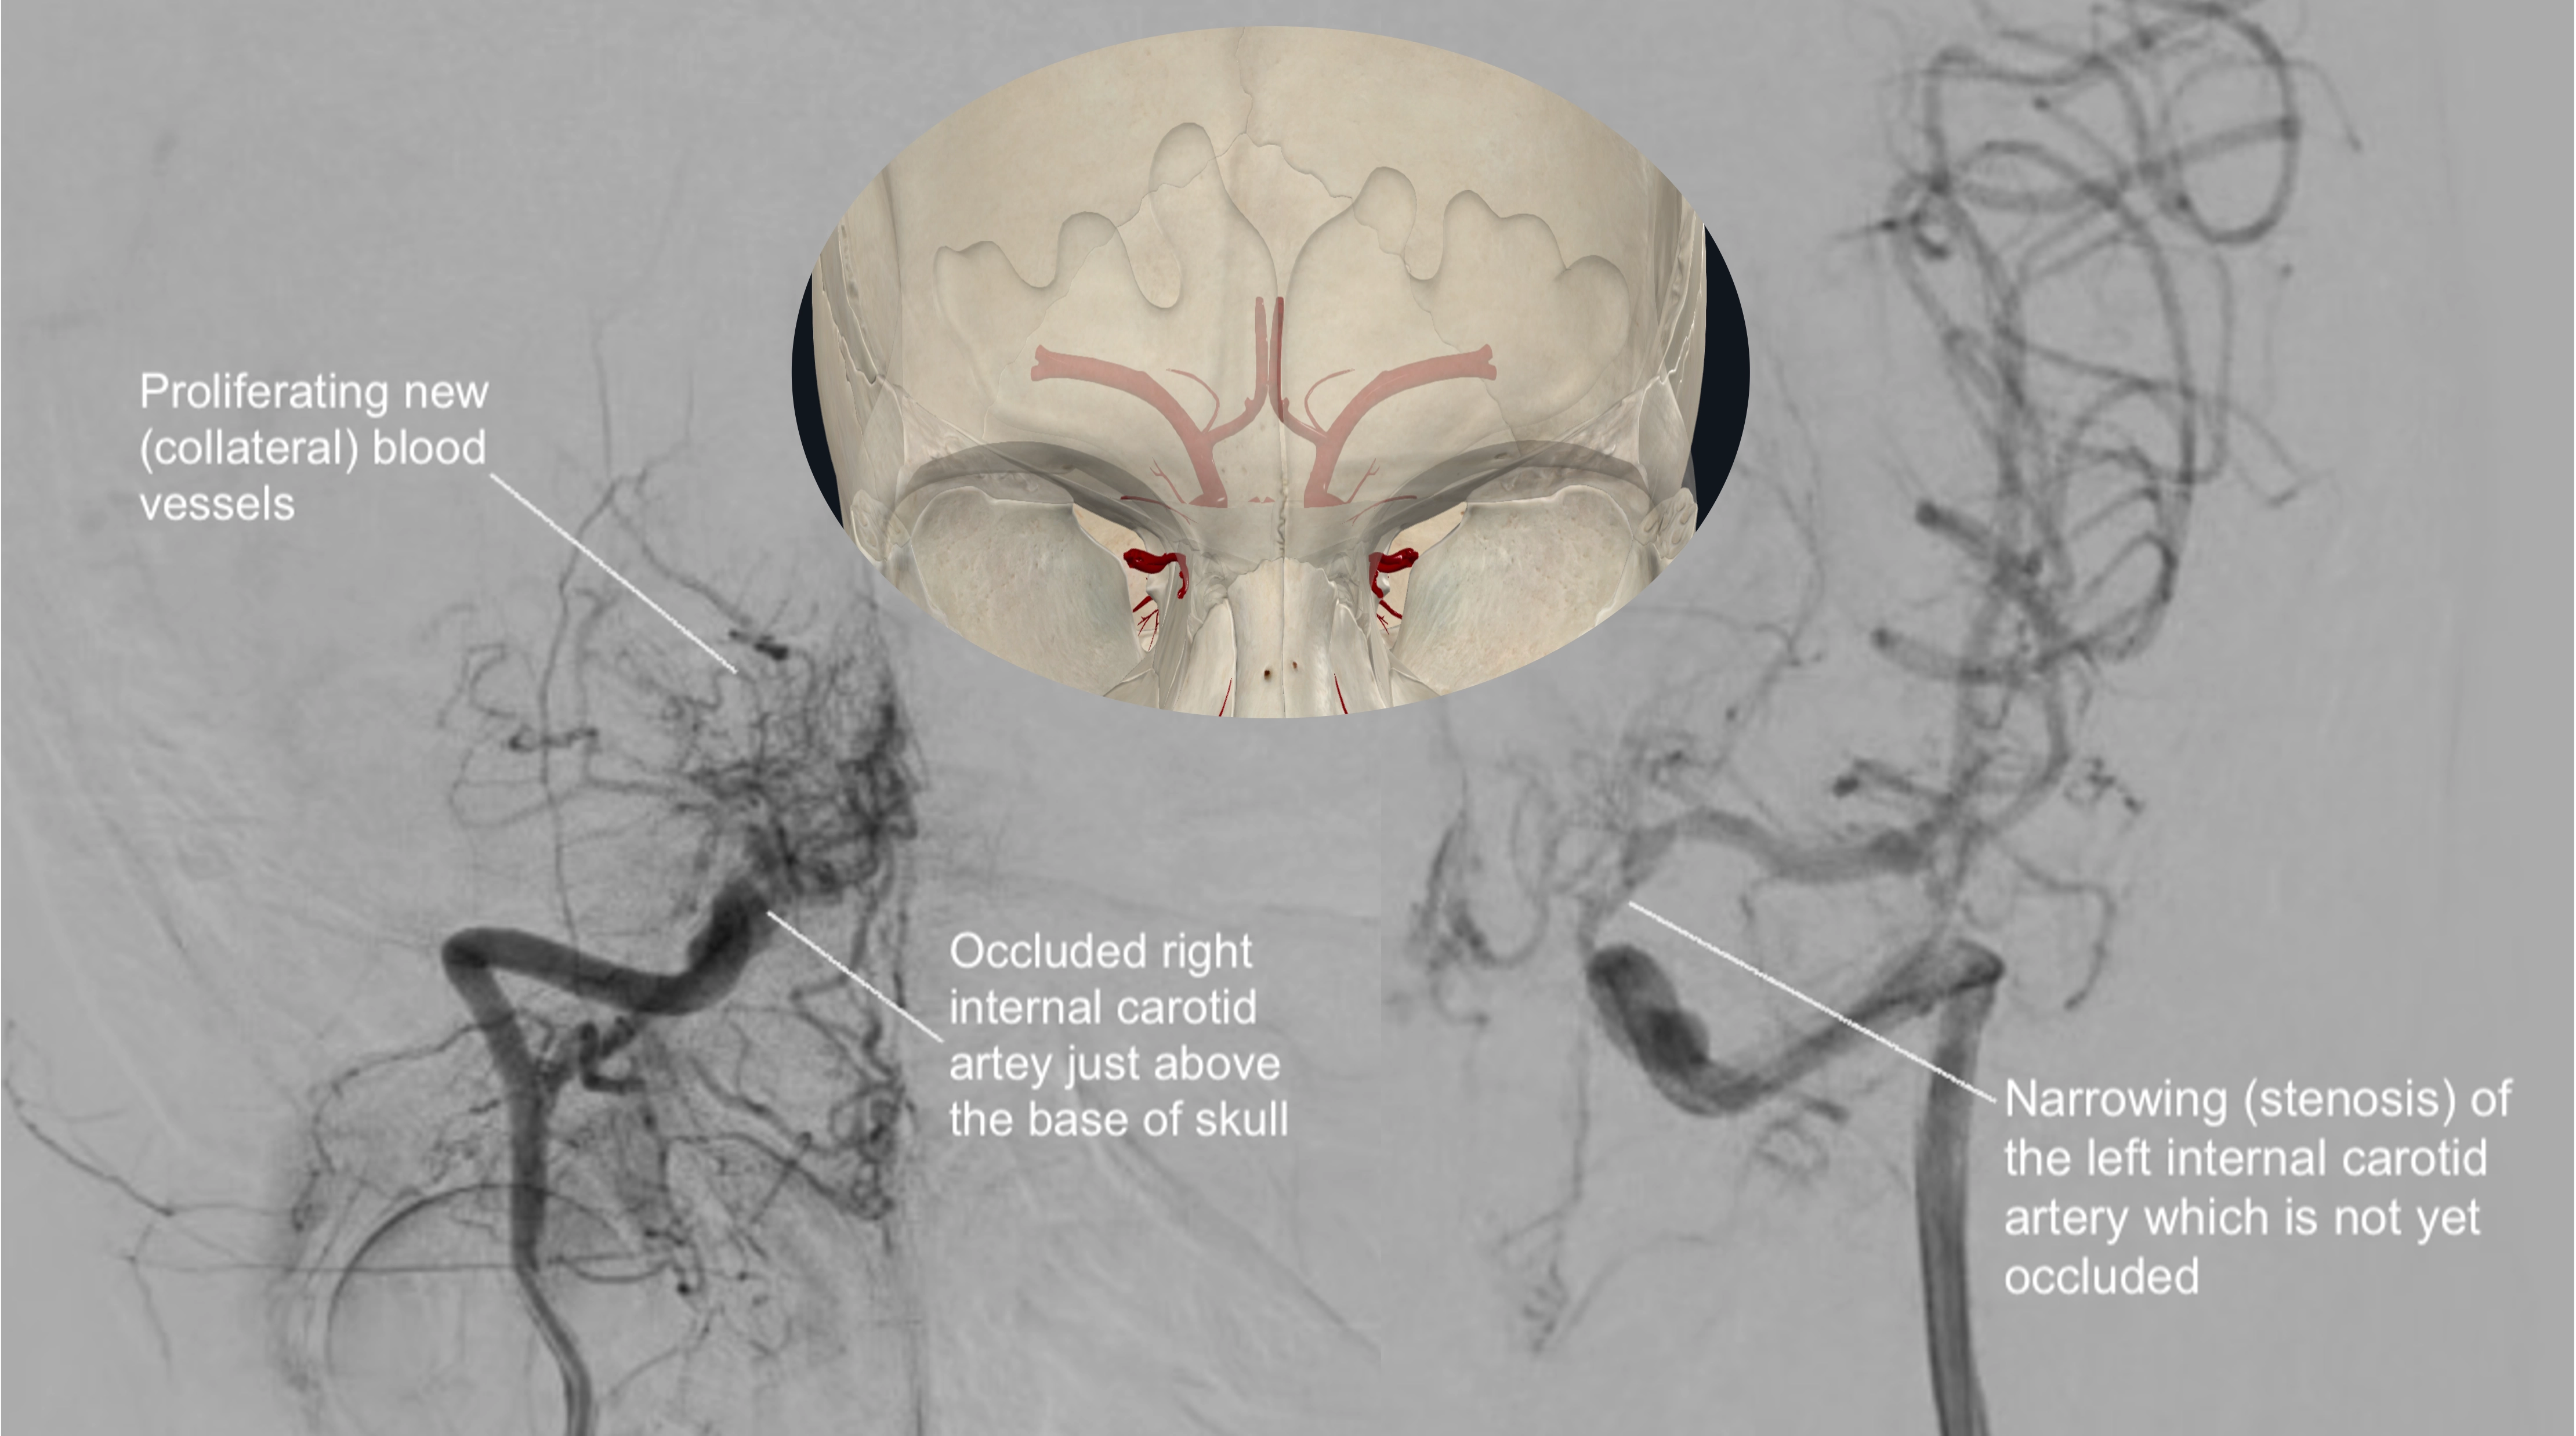

- 뇌혈관 조영술(Cerebral Angiogram): 가장 정확한 진단 방법 중 하나입니다. 사타구니 혈관을 통해 가느다란 도관(카테터)을 뇌 혈관까지 삽입한 후 조영제를 주입하고 X선 촬영을 하여 뇌 혈관의 협착 정도와 특징적인 모야모야 혈관을 직접 확인합니다.

모야모야병(Moyamoya disease)은 특별한 원인 없이 뇌 속 특정 혈관, 주로 내경동맥 끝부분이 서서히 좁아지거나 막히는 만성 진행성 뇌혈관 질환입니다. 혈관이 좁아지면 뇌 혈류량이 감소하게 되고, 부족한 혈류량을 보충하기 위해 막힌 혈관 주변으로 가늘고 약한 비정상적인 미세혈관들이 자라나게 됩니다. 뇌혈관 조영술 이미지에서 이 미세혈관들이 마치 '연기가 모락모락 피어오르는 모양'과 같다고 하여 일본어로 '모야모야(もやもや)'라는 이름이 붙었습니다.

병태생리 측면에서 보면, 뇌혈관 협착에 대응하여 생성된 미세 혈관망이 특징적인 '연기 모양'을 나타냅니다. 최근 "기계-생물학적 이론(Mechano-biological theory)"은 혈관 구조의 차이 등 여러 요인이 복합적으로 작용하여 광범위한 뇌혈관 폐색을 유발하고, 손상된 뇌에 혈액을 공급하기 위한 혈관 연결의 변화를 초래한다고 설명합니다. 일단 발병하면 혈관 폐색은 알려진 내과적 치료에도 불구하고 계속 진행되는 경향이 있습니다.